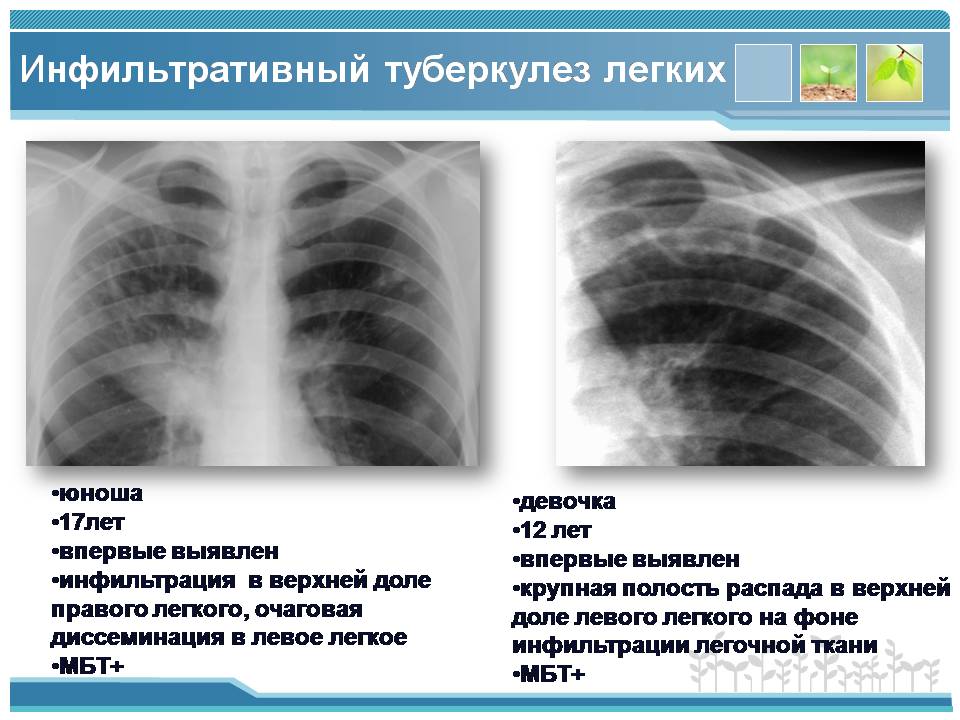

Очаговый и инфильтративный туберкулез презентация - 94 фото